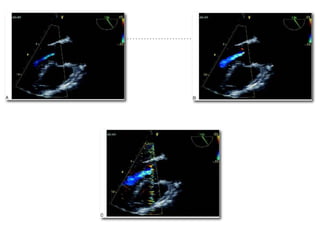

The Color Flow Doppler (CFD) provides a striking display of both

blood flow and the cardiac anatomy by superimposing the PWD

flow data on 2D images [29] [Figure 15]. It is useful in diagnosing the

abnormal flow as well as confirming the normal structures.

Figure 15: A mid esophageal, four-chamber view superimposed with color flow doppler showing mitral regurgitation. The vena contracta (VC) depicts the regurgita

Color flow Doppler TheColor Flow Doppler (CFD) provides a striking display of both blood flow and the cardiac anatomy by superimposing the PWD flow data on 2D images [29] [Figure 15]. It is useful in diagnosing the abnormal flow as well as confirming the normal structures. Figure 15: A mid esophageal, four-chamber view superimposed with color flow doppler showing mitral regurgitation. The vena contracta (VC) depicts the regurgita

• 100.

Color maps The PWDused for color mapping, records the mean velocity data from multiple sample volumes - color packets along each scan line. This velocity data is then color-coded; blue indicates flow away from the transducer and red is the flow toward the transducer. The color bar on the screen provides a reference frame for interpreting the colors. The color flow maps are then integrated with 2-D imaging to provide a real-time display.